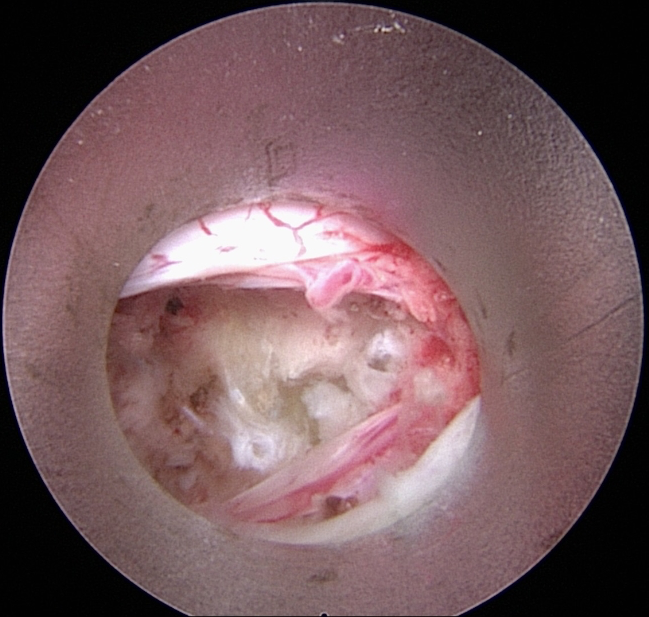

Πλάγια προσπέλαση

Πρόκειται για μια ακόμα πιο ειδική μέθοδο, κατά την οποία εισερχόμαστε μέσω του μεσοσπονδύλιου τρήματος και αποκτούμε πρόσβαση κατευθείαν στην δισκοκήλη χωρίς να χρειάζεται αφαίρεση οστικού τμήματος. Αποτελεί την λιγότερο επεμβατική μέθοδο όλων στην σπονδυλική στήλη, αφού χρησιμοποιεί φυσικά τρήματα για την είσοδο στον σπονδ. σωλήνα.